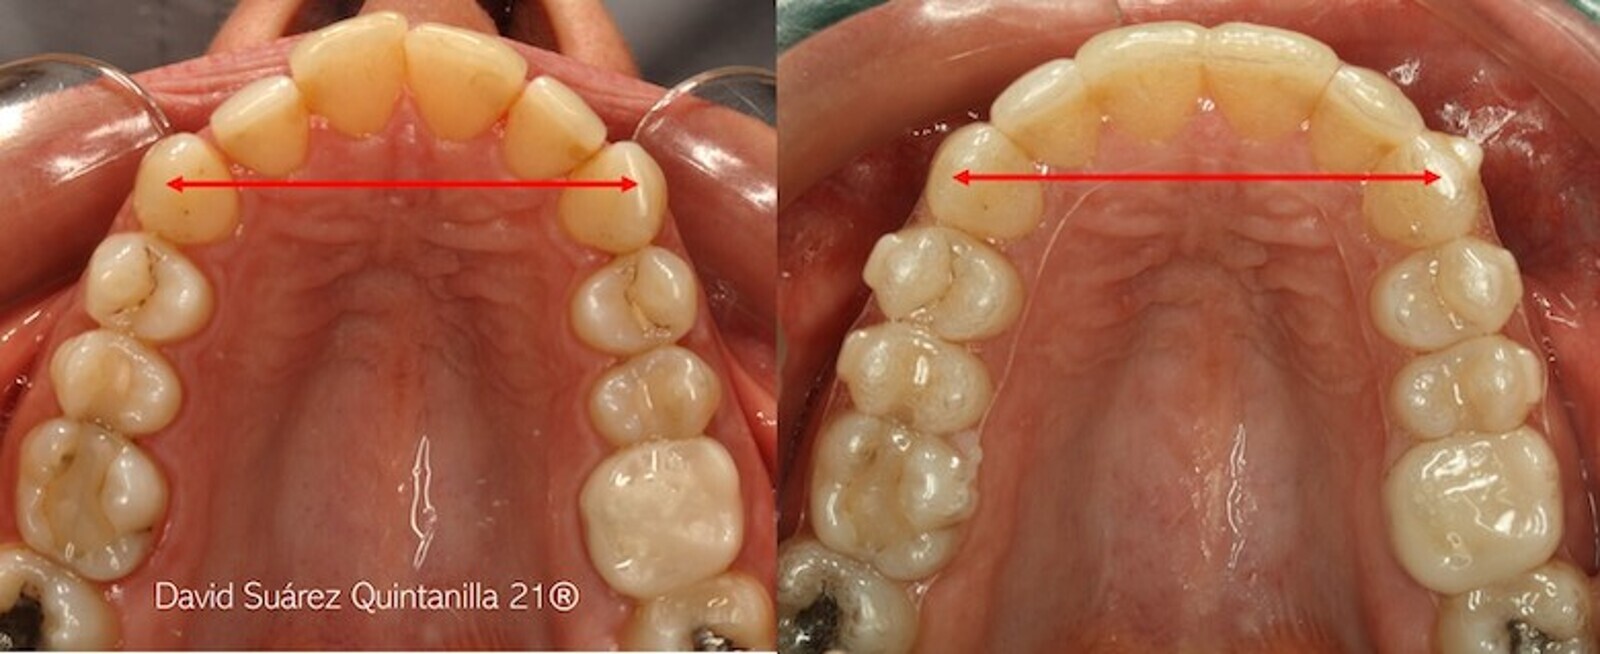

• Los ataches activos.

Este sencillo esquema no pretende diseñar alineadores sino ofrecer una sencilla herramienta para entender las bases de la planificación, antes de que cada uno opte por una u otra compañía y sus programas y clincheck específicos. Por ejemplo, en el caso del distalamiento secuencial de molares (DSM) en el maxilar (figura 43), el discente ha de entender el concepto de anclaje recíproco y diferencial, iniciando su plan de tratamiento con el anclaje de los dientes mesiales a los segundos molares (figura 43), para iniciar su distalamiento con ataches (figura 44). Después iniciamos el distalamiento del 16 y 26 para, acto seguido, crear un nuevo grupo de anclaje posterior molar que nos permita iniciar el distalamiento de los premolares (figura 45), aplicando la regla del 50% (figura 46): al estar distalado el diente más posterior el 50%, iniciamos el distalamiento del inmediatamente mesial y así sucesivamente (figura 46).

Figura 43. Distalamiento secuencial de molares en el maxilar.

Figura 44. Inicio de distalamiento con ataches.

Figura 45. Nuevo grupo de anclaje posterior molar para poder iniciar el distalamiento de los premolares.

Figura 46. Distalamiento del mesial aplicando la regla del 50%.